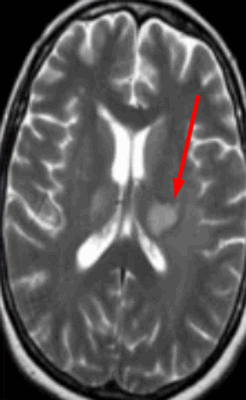

Очаг демиелинизации на МРТ

Обычно очаги демиелинизации выглядят как множественные мелкие участки гиперинтенсивного МР-сигнала, расположенные в одном или нескольких отделах головного мозга. По степени их распространенности, давности и одновременности возникновения врач судит о масштабах развития заболевания.